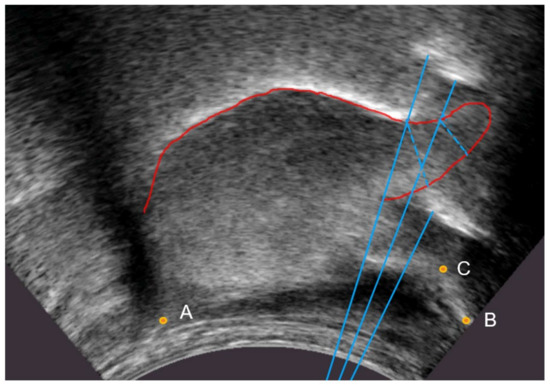

3.1.3. Ultrasound Keypoint Labelling